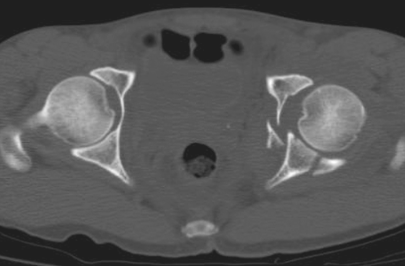

1、双柱髋臼骨折:

双柱髋臼骨折(图9-10)包括前柱和后柱,并延伸到闭孔环和髂骨翼,是最常见的髋臼骨折之一。在X线片上,前柱和后柱的骨折受累特征分别是髂耻线和髂坐线的破坏。然而,这些线的破坏也可能出现在其他骨折模式(例如横行骨折)。闭孔环和髂骨受累也必须存在,作为双柱髋臼骨折分型。在前后位X线片上,髂骨翼的骨折延伸并不总是很明显;但在倾斜的Judet位或CT上常常可以被发现。

图9 双柱髋臼骨折a.骨盆正位片;b、c.双侧斜位骨盆X线片;d.轴位CT扫描;e.矢状面重建CT扫描。直线箭头:髋臼骨折;箭头:闭孔环中有破裂;弯曲的箭头:骨折延伸到髂骨翼。

图10 双柱髋臼骨折并有spur征a.闭孔斜位X线片;b.轴位CT图像显示骨折标志(直线箭头),代表骨折移位涉及坐骨支(直线箭头)。请注意,坐骨支(箭头)不再连接髋臼的负重部分。

在CT上,可以看到前柱和后柱的骨折受累,骨折可能呈粉碎性。闭孔环的断裂破坏具有可变的外观,耻骨上支的骨折可能发生在耻骨髋臼连接处。另外,如果不移位,可能难以确定耻骨下支的骨折。主要骨折线从髋臼向髂骨翼延伸,特征在于冠状面上。

如果存在的话,双柱断裂的特征性标志是“刺征(spur)”标志(又称“马刺征或枪刺征”)(图10a、b)。这个标志代表了髂骨翼骨折的坐骨支撑的后位移,这实质上将髋臼的顶部与轴骨骼断开。当发生这种情况时,躯干和上身的重量将不再受髋臼支撑。在X线片和CT影像中,骨折标志表现为在上髋臼水平向后延伸的骨碎片。连续CT图像的评估显示骨折,将坐骨神经与髋臼顶分开。